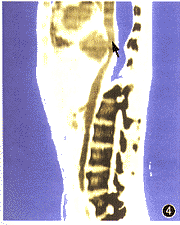

主动脉假性动脉瘤3例。CTVE表现为动脉管壁于某处突然中断,在中断处有一裂隙与周围一不规则形大腔相通,同时仍可看到正常的动脉管腔(图4~6)。

图4~6 主动脉假性动脉瘤。图4为多平面重建法(MPR)图像,示胸主动脉假性动脉瘤。图5为CTVE图像,示正常降主动脉、裂口、假腔。图6为CTVE图像,示腹主动脉假性动脉瘤裂

3.主动脉假性动脉瘤:可发现动脉壁破裂的位置、裂口形态及长度等, 这是现有的其他检查手段所无法做到的。本组病例中,3例假性动脉瘤均发现了破口位置,为临床提供了强有力的依据。值得一提的是,为我院1例高难度腔内隔绝术治疗巨大腹腔干假性动脉瘤的手术提供了极有价值的信息,保证了手术的成功,是其他检查手段无法取代的。